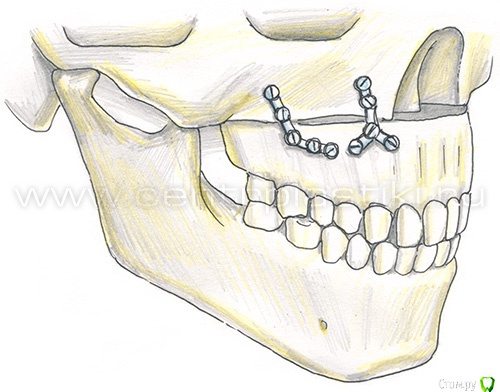

LEOnchik Опубликовано 3 апреля, 2015 Поделиться Опубликовано 3 апреля, 2015 Может у Вас интеграция в кортикальной кости происходит, гений?? Встречный вопрос могу задать?В данном случае проходит интеграция винтов, которыми прикручены пластины для остеосинтеза? Ссылка на комментарий